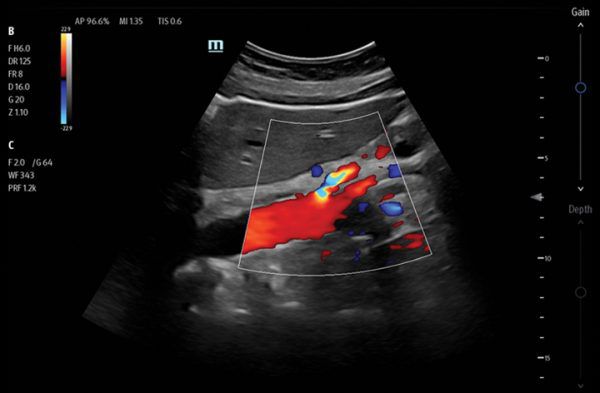

Clinical Images